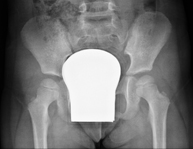

- RX Pelvis

Procedimiento mediante el cual, utilizando rayos X, se obtienen imágenes de la pelvis para su estudio, especialmente de los huesos pélvicos.

- RX Caderas pediatría

Estudio que, utilizando los rayos X, permite obtener una imagen de los huesos de la cadera y descartar luxaciones.

- RX Caderas